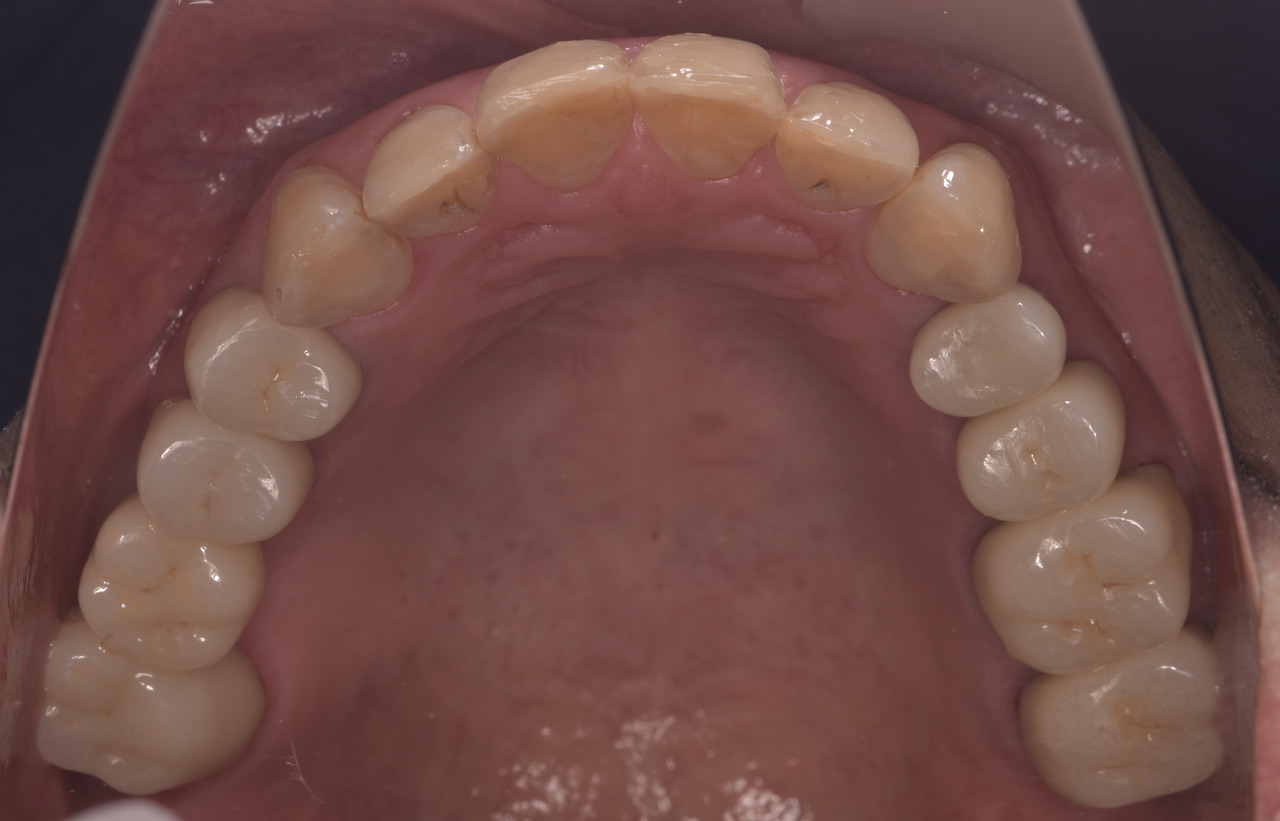

全顎的に複数の治療部位で、インプラント・ブリッジ・ダイレクトボンディング・セラミッククラウンなど、適切な治療方法を組み合わせて包括的な治療を進めました。

治療後